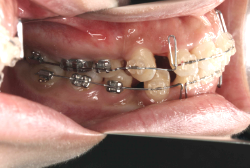

「乳歯が生え替わらない」という主訴で来院したケースです。 診断の結果、「左上永久犬歯が第一小臼歯後方上部に埋伏しているため、左上乳犬歯が晩期残存している症例」と判明しました。

このような症状の場合は、手術で埋伏している永久歯に金具を取り付け、矯正装置で牽引する必要があります。同時に凸凹の解消と前突した前歯を内側に入れるために上下左右の小臼歯を抜歯させて頂くことといたしました。

この方の場合は、マルチブラケット装置にて治療を開始し、治療期間2年3ヶ月で終了しました。犬歯の牽引距離が非常に大きかったため当院の平均治療期間よりも大幅に期間がかかりましたが、埋伏犬歯を完全に正しい位置まで誘導することができました。同時に 前歯の前突と配列の凸凹も解消しました。

マルチブラケット装置は、装置装着時より数日から2週間程度強い不快感疼痛が有りますが、本症例場合は埋伏歯を開窓手術し、遠く離れた位置に矯正器具が付いていますので強い違和感が生じ、歯ブラシも届きにくく口腔衛生状態を保つのにはかなりの努力が必要です。条件の悪い場所に接着されているため、装置が外れやすく日常生活上もかなり配慮が必要となります。

また、埋伏歯は移動距離が大きくなることが多く、歯根吸収のリスクが高まりますので、移動と休止にゆとりのある治療間隔が必要です。